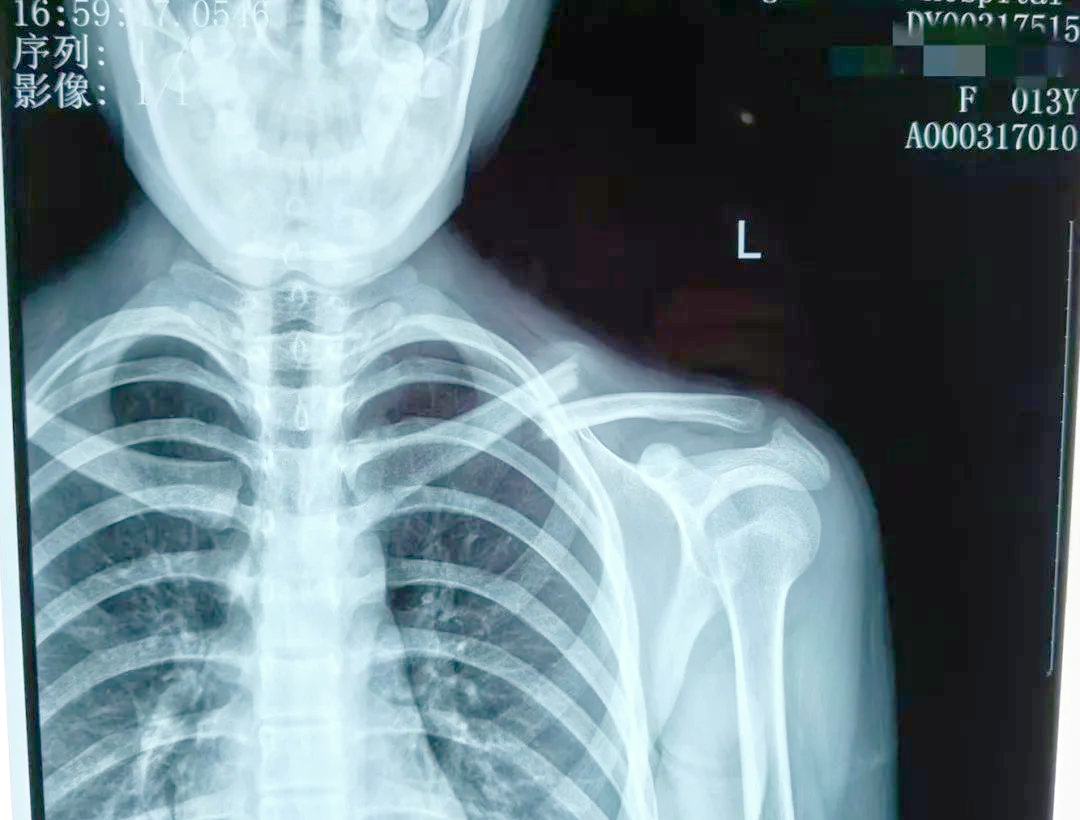

锁骨拍片位置

左侧锁骨远端骨折保守治疗记录